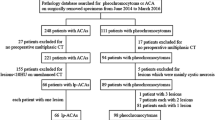

We retrieved clinical and radiological data from 30 consecutive patients with histologically confirmed PCCs, who have been evaluated at the Endocrinology and Diabetes Prevention and Care Unit of the S. Orsola Policlinic between April 2007 and December 2018. We included patients diagnosed with pheochromocytoma either during the study of resistant hypertension (n = 20) or during the hormonal workup of an incidentally discovered adrenal mass (incidentaloma) (n = 10). The study conforms to the ethics guidelines of the Declaration of Helsinki, and data collection and analyses had already previously been approved by our Institutional Review Board. All patients provided informed written consent for the processing of personal data according to The Italian Data Protection Authority law (legislative decree no. 196 of 2003 and no. 101 of 2018).

Cluster analysis

The cluster analysis based on radiomic features was performed on 25 patients, because 5 had incomplete clinical data; the analysis identified 2 clusters, with 18 patients in cluster 1 and 7 patients in cluster 2. The dendrogram of the cluster analysis is shown in Fig. 1.

The radiomic, clinical, and histopathological characteristics of the two clusters are shown in Table 3. When compared to cluster 2, patients belonging to cluster 1 showed higher compacity (15.4 vs 8.9, p = 0.001), lower volume (10.2 mL vs 42.7 mL, p < 0.001), lower maximum HU value detected in the unenhanced (86.1 vs 94.7, p = 0.040) and in the arterial (197.4 vs 241.9, p = 0.021) phase, and higher minimum HU value in the portal phase (− 24.2 vs − 53.3, p = 0.046). Patients belonging to cluster 2 had higher systolic and diastolic blood pressure values at the time of diagnosis (p = 0.025), and higher GAPP score (4 vs 6, p = 0.05), histological pattern (1–2, p = 0.039), and comedonecrosis (0% vs 50%, p = 0.013) at histopathology, than subjects in cluster 1. Even if it did not reach the significance threshold, it is worth noting that all patients with metastatic disease were included in cluster 2 (0–28.6%, p = 0.07).